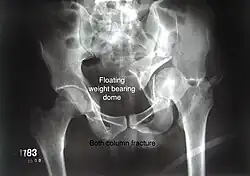

Combined both column fractures These are the most complex injuries. Here the weight bearing roof or dome of the acetabulum is a floating piece. This adds to complexity of management.

Anterior column This fracture is uncommon, typically occurring when the injuring force is applied from the side, against the greater trochanter of the femur bone, as in a fall on the side or being hit on the side. Depending on the location, the fractures are described as very low, low, intermediate and high anterior column fracture. Anterior column + posterior hemi transverse In this variety of fractures, the posterior or ilio ischial column is broken as a transverse fracture, while the anterior or ilio pubic column is broken into multiple pieces. Part of the weight-bearing dome in this variety of fractures is still attached to that part of the iliac wing, which forms part of the iliac joint. This type of injury has to be differentiated from both column fractures, where the weight-bearing dome is a floating piece not attached directly to the bone-forming sacroiliac joint.

Transverse In this variety of fracture, the innominate bone is broken such that the upper part consists of ilium with weight bearing dome and the lower part consists of ischium and pubic bones. It typically occurs when the injuring force is applied from the side, against the greater trochanter of the femur bone, as in a fall on the side or being hit on the side. This is a two part fracture, but though both columns are broken, it is not a true both-column fracture, as the weight bearing dome is still attached to main ilium.

In this variety of fracture, the innominate bone is broken such that the upper part consists of ilium with weight bearing dome and the lower part consists of ischium and pubic bones. It typically occurs when the injuring force is applied from the side, against the greater trochanter of the femur bone, as in a fall on the side or being hit on the side. This is a two part fracture, but though both columns are broken, it is not a true both-column fracture, as the weight bearing dome is still attached to main ilium.